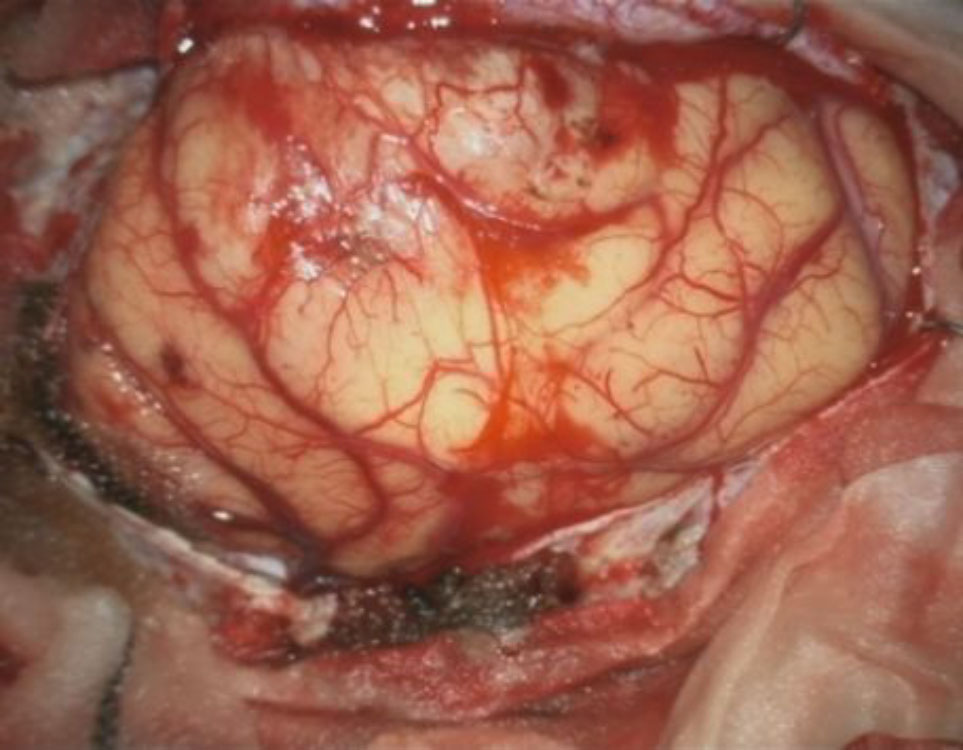

618

'25年4月

40代

小脳血管芽腫

頭蓋内腫瘍摘出術

No.’25_20 手術前1

No.’25_20 手術前2

No.’25_20 摘出 前

No.’25_20  摘出 中

No.’25_20 摘出 後